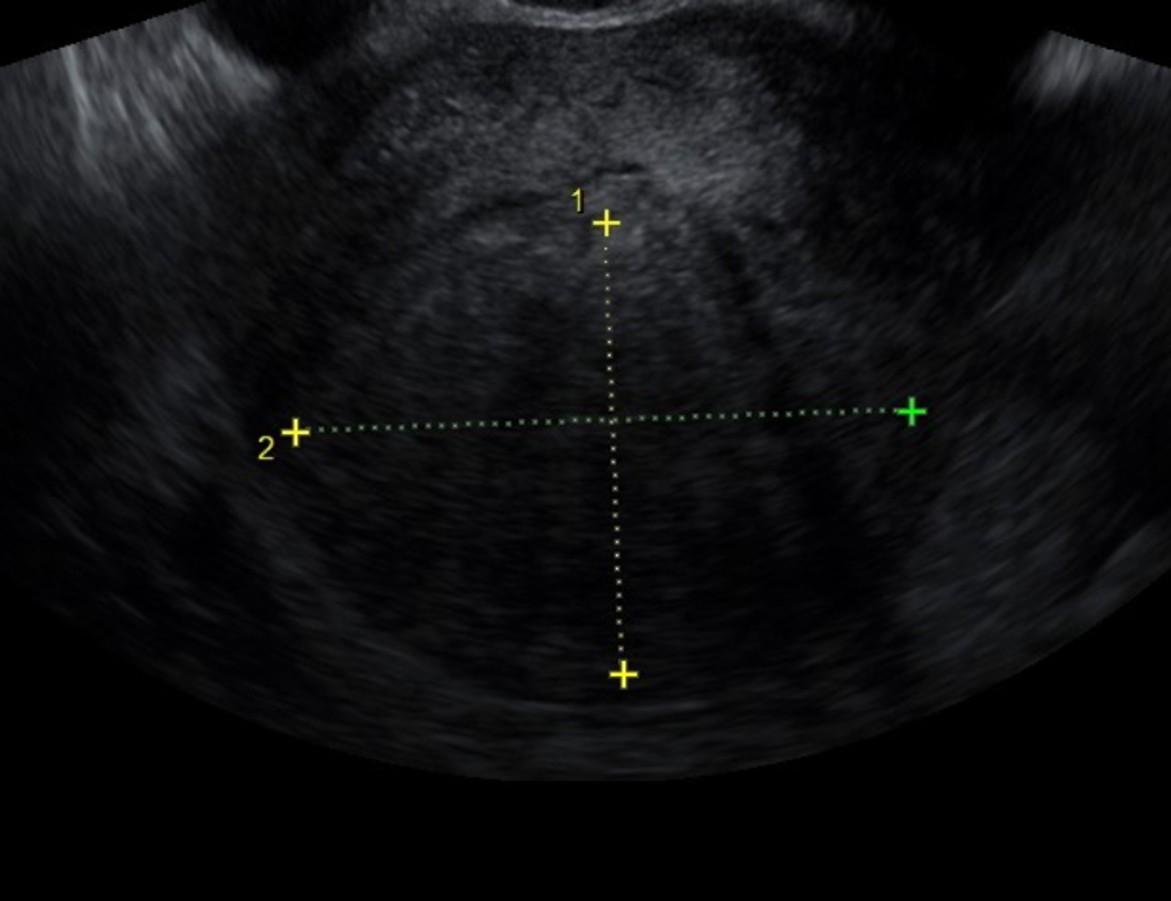

LIVE · Ultrasound Guide

Depth 42mm · Gain 68%

병변만을 선택하는

초음파 유도 치료

실시간 질 초음파 가이드 하에서 병변 중심부만을 정밀 응고하여 자궁 내막과 정상 조직 손상을 최소화합니다.